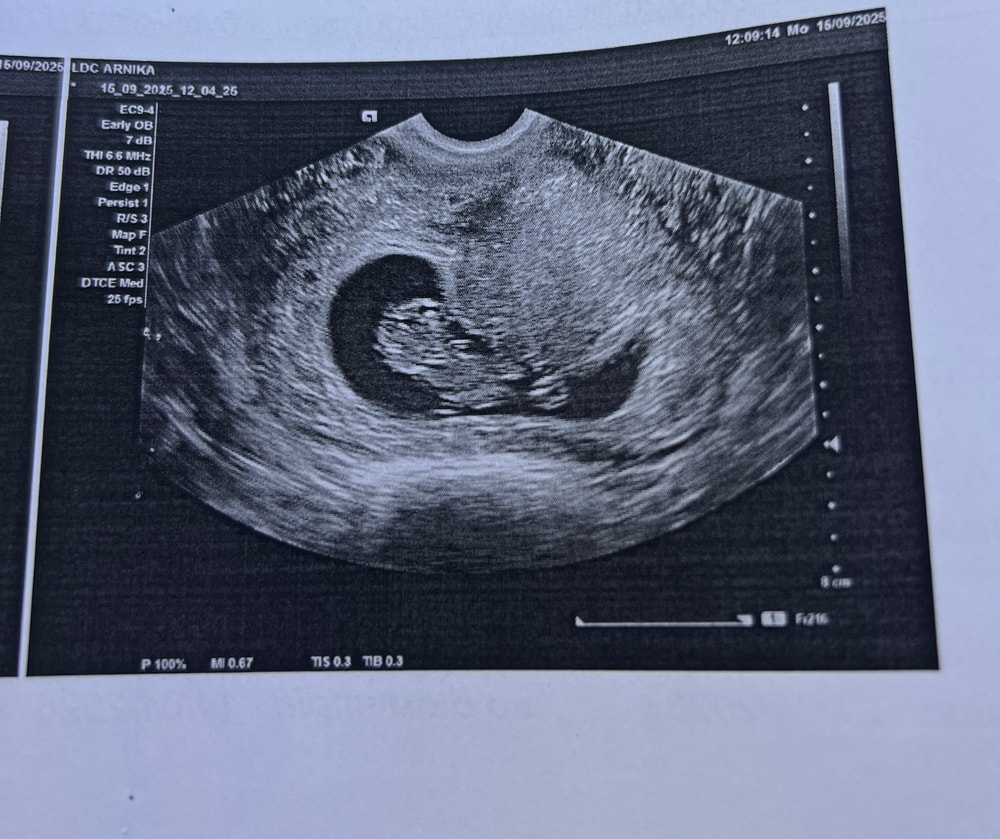

УЗИ 9 недель

Обследования, узи, анализыВчера была на узи, акушерский срок 9 недель но по узи поставили 10 недель, узист сказала что мы очень крупненькие и не соответствуем 9 неделям😁 и тут я вспомнила как на первом узи нам сказали как все плохо, отстаем на 2 недели и наверное плодное яйцо пустое. Вот, прилагаю фото «пустого» яйца😂

КТР малыша 31,2 мм, толщина эмбриончика 9мм, сб + 166 ударов, структуры мозга хорошие, активничает там в животике😁 так мило было, он крутился как сам хотел, она только начала датчиком водить как он оттолкнулся ножкой, отвернулся от нас и ручку поднял🥹